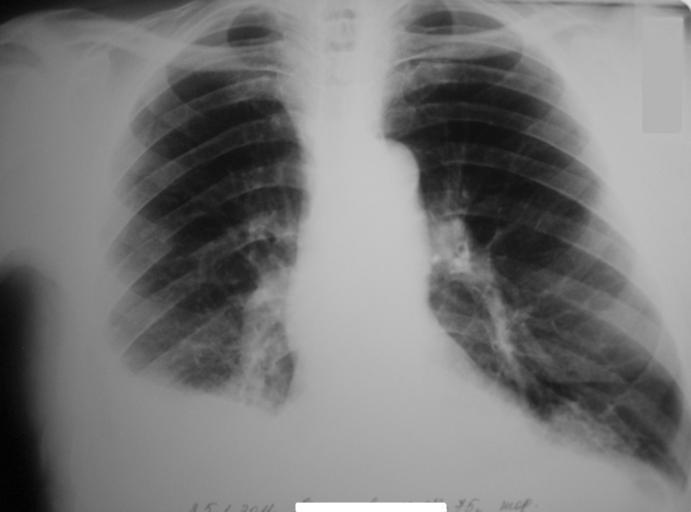

| View Original: | –У–µ–Љ–Њ—В–Њ—А–∞–Ї—Б, –њ–µ—А–µ–ї–Њ–Љ—Л —А—С–±–µ—А.jpg (3066x2271) | |||

| Keywords: –У–µ–Љ–Њ—В–Њ—А–∞–Ї—Б, –њ–µ—А–µ–ї–Њ–Љ—Л —А—С–±–µ—А.jpg ru –Ч–∞–Ї— —Л—В—Л–µ –њ–µ— –µ–ї–Њ–Љ—Л VI VII VIII IX — —С–±–µ— —Б–њ— –∞–≤–∞ –Я— –∞–≤–Њ—Б—В–Њ— –Њ–љ–љ–Є–є –≥–µ–Љ–Њ—В–Њ— –∞–Ї—Б –°–Њ–±—Б—В–≤–µ–љ–љ–∞—П —Д–Њ—В–Њ–≥— –∞—Д–Є—П –Ъ–ї–µ—В–Ї–Є–љ – –∞–Ї—Б–Є–Љ –Х–≤–≥–µ–љ—М–µ–≤–Є—З 2011-01-30 Cc-zero Injuries to the thorax X-rays of the chest | ||||